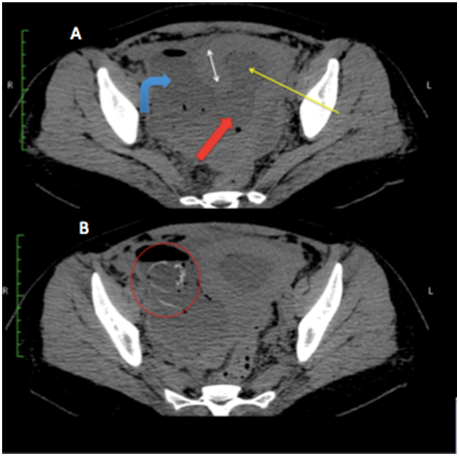

Trans-abdominal ultrasound of pelvic organs (Figure 1) revealed bulky uterus with defect in right postero-lateral wall (3 cm in maximum transverse diameter) of uterus, with an irregular heterogenous collection in right adnexa, which was communicating with endometrial cavity. Multiple tiny internal echoes were present in the collection, likely due to air, suggestive of infected collection. For confirmation and proper characterization non-contrast CT scan was performed.

Figure 1 Trans-abdominal ultrasound shows defect in the right postero-lateral wall of uterus (thick red arrow) with echogenic fluid filled collection in endometrial cavity (thin yellow arrow), which is communicating with collection in right adnexa (curved blue arrow). Right double arrow represents normal myometrium.